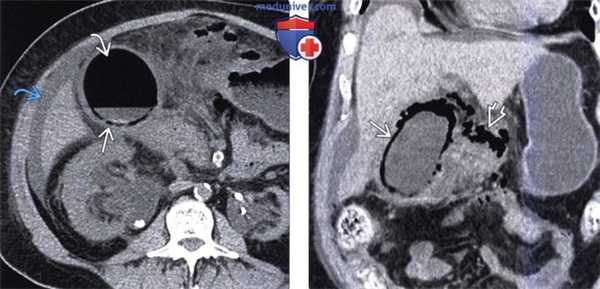

(Слева) На аксиальной КТ без контрастного усиления у пожилой женщины, страдающей сахарным диабетом, в утолщенной стенке и в просвете желчного пузыря определяются включения газа. Обратите внимание на выраженные воспалительные изменения жировой ткани вокруг желчного пузыря, а также асцит..

(Справа) На корональной КТ без контрастного усиления у этой же пациентки определяется газ в стенке желчного пузыря и рядом с ним, что свидетельствует о перфорации. Эмфизематозный холецистит характеризуется высоким риском возникновения гангрены и перфорации стенки.